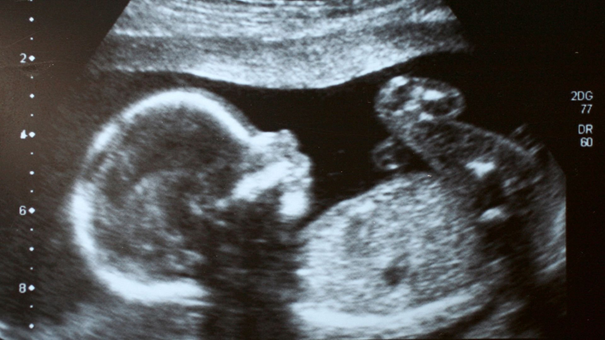

Üçlü tarama testi

Gebeliğin 16-19 haftaları arasında yapılan Down sendromu gibi sık görülen kromozomal hastalıkların taraması için kullanılan bir testtir. Ayrıca nöral tüp defekti taramasın için de kullanılmaktadır. Öncelikle bebeğin ultrasonografik değerlendirme ile kafa çapı ölçülerek hangi hafta ile uyumlu olduğu kaydedilir. Anneye ait bilgiler doğum tarihi, son adet tarihi, kilosu, sigara kullanımı, daha önce nöral tüp defektli ve kromozom anomalili bebek öyküsü olup olmadığı, akraba evliliği, ultrasonografiye göre gebelik haftası, usg tarihi, diyabet olup olmadığı, tek mi, çoğul mu gebelik olduğu kaydedilir. Ardından anneden kan alınarak HCG (human chorionic gonadotropin) hormonu, bebeğin karaciğerinden salgılanarak anneye geçen AFP (alfa fetoprotein) hormonu ve uE3’ (konjuge olmayan estriol) düzeyleri belirlenir. Tüm bilgiler istatistiksel olarak analiz edilerek risk katsayısı belirlenir.